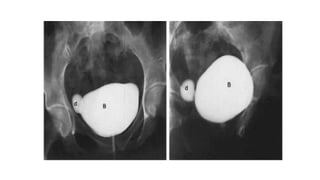

• #27 Voiding cyctourethrography in AP and oblique projections sowing bladder diverticulum